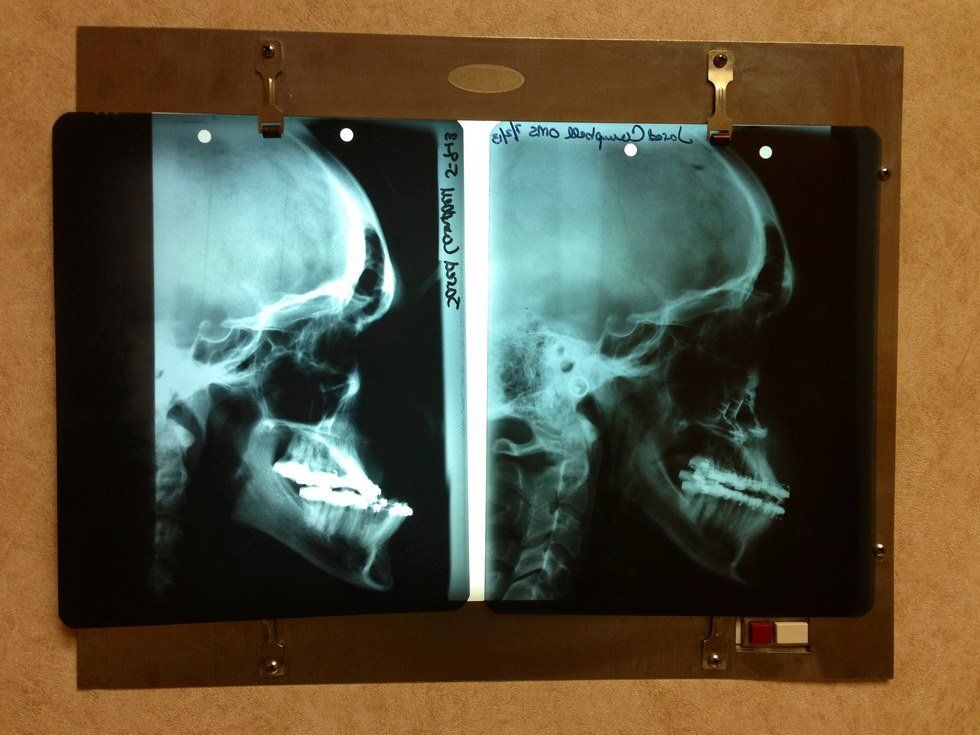

For thirteen years, we were working towards having a jaw surgery that would fix my incorrect bite. Since I was 6 years old, I went to orthodontic appointments, had head gears, pallet expanders, four different sets of braces, various retainers, power chains, numerous spacers (or as I like to refer to them as “the devil’s favorite torture device”), countless rubber bands, many teeth pulled, and other orthodontic-related things (with names I have no idea how to even begin to spell or look up on Google).

When I was 12 years old, my upper jaw stopped growing while my lower jaw continued at an accelerating rate. As you can imagine, that’s slightly problematic when you haven’t even gone through puberty or your junior high/high school growth spurt but your upper jaw has decided, “Naw, I think I’m good. I’ll just stay here, thanks!” By senior year of high school, only two of my teeth touched; biting and eating was a difficult task. Something like biting a carrot or eating corn on the cob became simply impossible.

The surgery is called a maxillary advancement and mandibular setback. Basically, surgeons removed part of my lower jaw (by scrapping and cutting the bone) and brought it backward and then broke my upper jaw and moved it forward. You might be thinking, “Oh gosh! That must have been very painful.” Luckily, they had me on such strong medication that I didn’t feel a thing besides the catheter (another one of the devil’s favorite torture devices). Although I was never in pain even during the recovery process, you can imagine how bad the swelling was. But, no need to imagine -- there’s photographic evidence: